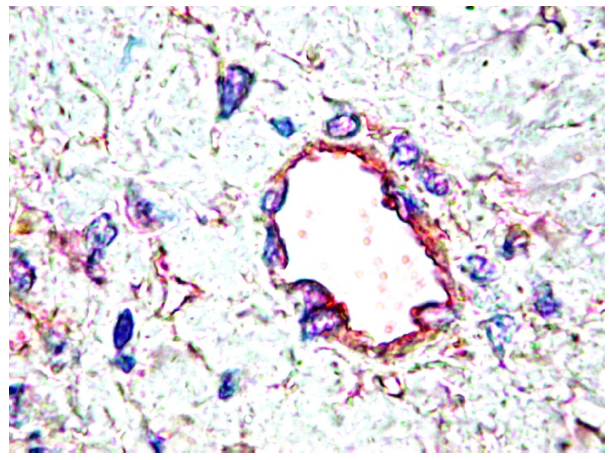

3. PDGF/PDGFR and Vascular Development

- Gerhardt, H.; Betsholtz, C. Endothelial-pericyte interactions in angiogenesis. Cell Tissue Res. 2003, 314, 15–23. [Google Scholar]

- Hellström, M.; Kalén, M.; Lindahl, P.; Abramsson, A.; Betsholtz, C. Role of PDGF-B and PDGFR-beta in recruitment of vascular smooth muscle cells and pericytes during embryonic blood vessel formation in the mouse. Development 1999, 126, 3047–3055. [Google Scholar]